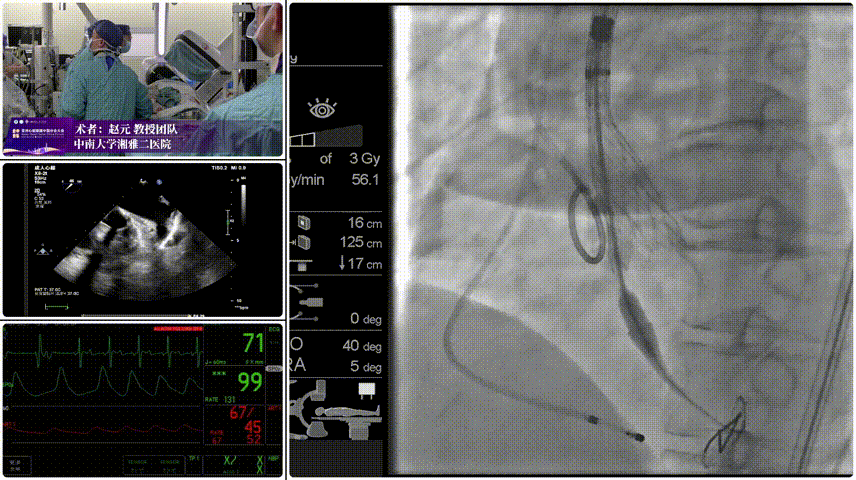

Step 1.柔顺过弓:精湛手术操作+优异通过性能、复杂弓形无任何辅助一次通过。

瓣膜输送系统的柔顺过弓设计成为本次手术的核心亮点。系统采用短瓣架设计、易过弓专利技术与超滑亲水涂层,配合内联鞘小尺寸设计(等效 14F),完美适配细入路血管。手术中,介入团队在 DSA 引导下缓慢推进输送系统,凭借器械优异的柔顺性,在锐角弓解剖结构中实现一次性柔顺过弓,全程未出现器械卡顿、血管牵拉或钙化斑块剐蹭现象,过弓过程仅耗时1分钟,大幅降低了卒中与夹层风险。此外,内联鞘小尺寸设计有效减轻了对股动脉血管壁的机械损伤,术后血管闭合良好,未出现出血、血肿等并发症。

手术过程与术后转归